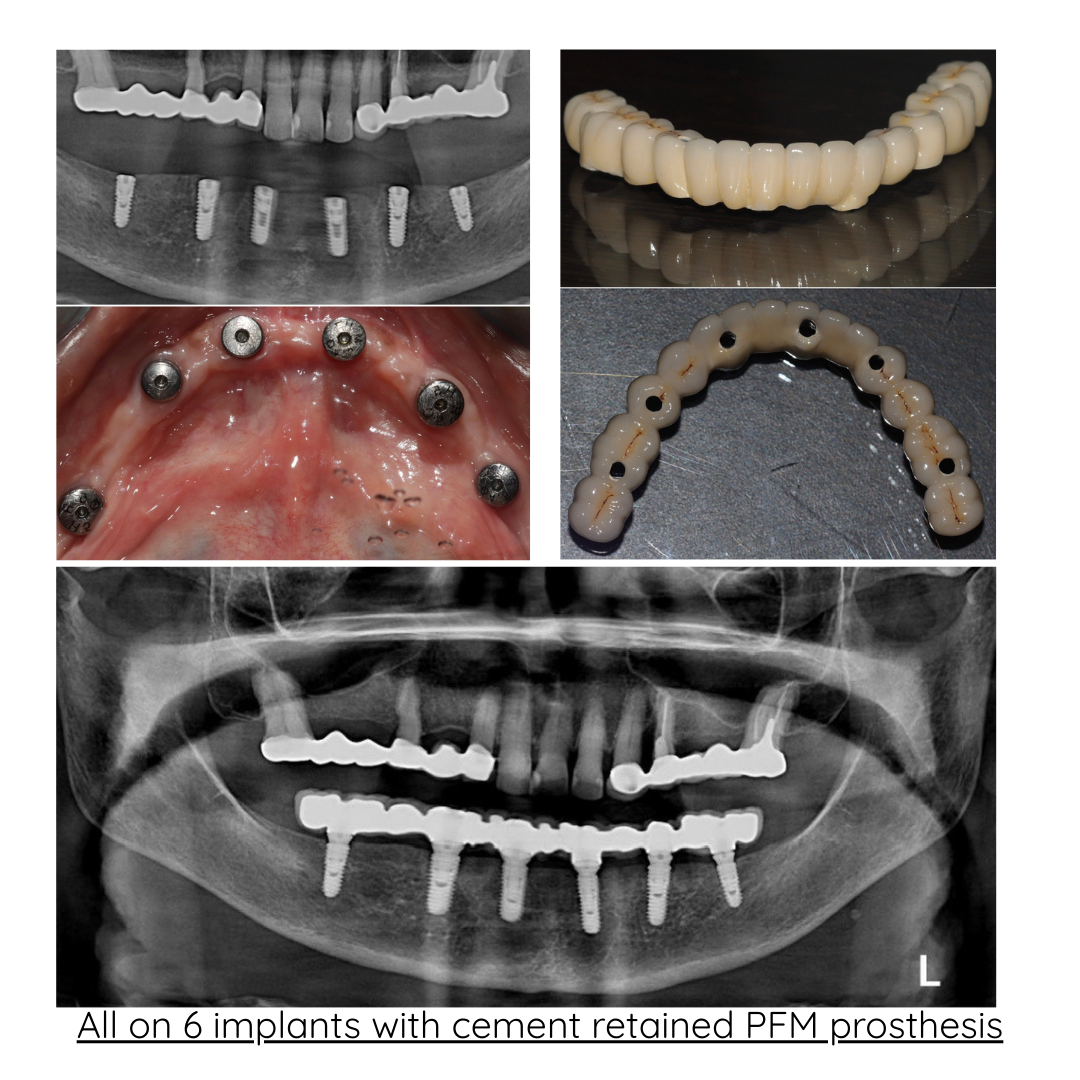

| All-on-6 (per arch) | ₹2,00,000 – ₹4,50,000 |

Our clinic uses advanced digital implant dentistry, guided by one of Pune's top expert dentists, including CBCT 3D scans, intraoral scanners, and precision-guided planning to ensure accurate implant placement, faster healing, and predictable results.